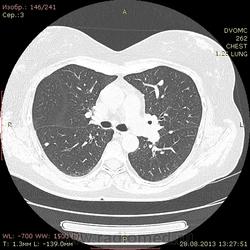

1961 г.р. В течение около 2х недель мучает сильный кашель, температура не поднималась, терапевны назначали антибиотики. Пропила неделю - без какого либо улучшения. Около полутора недель назад делали флюшку - без инфильтративных, корни немного расширены, структурны. Снгодня на флюшке появилась округлая тень слева. Решили сделать КТ - и вот результат.

Множественные мягкотканные мелкие узелки, лимфоаденопатия. Туберкалез? Саркоидоз? Mts? Не знаю чего и думать...прошу помощи.

1. Внутригрудная лимфоаденопатия. 2.Участки снижения пневматизации легочной ткани по типу "матового стекла". 3. Наличие в обоих легких узелковых образований (гранулем), преимущественно прилежащих к костальной, междолевой и межсегментарной плевре. Комплекс симптомов, наиболее характерен для Саркоидоза легких и ВГЛУ. Показано гистологическое подтверждение: трансбронхиальная внутрилегочная биопсия (информативность до 80% или медиастиноскоия и медистинотомия (информативность до 95%).

Лимфапролиферативное заболевание (ЛГМ, лимфома) vs саркоидоз. Нет тут туберкулеза.

На туберкулез легких не похоже.Лимфаденопатия. Метастазы. В меньшей степени вероятен саркоидоз.